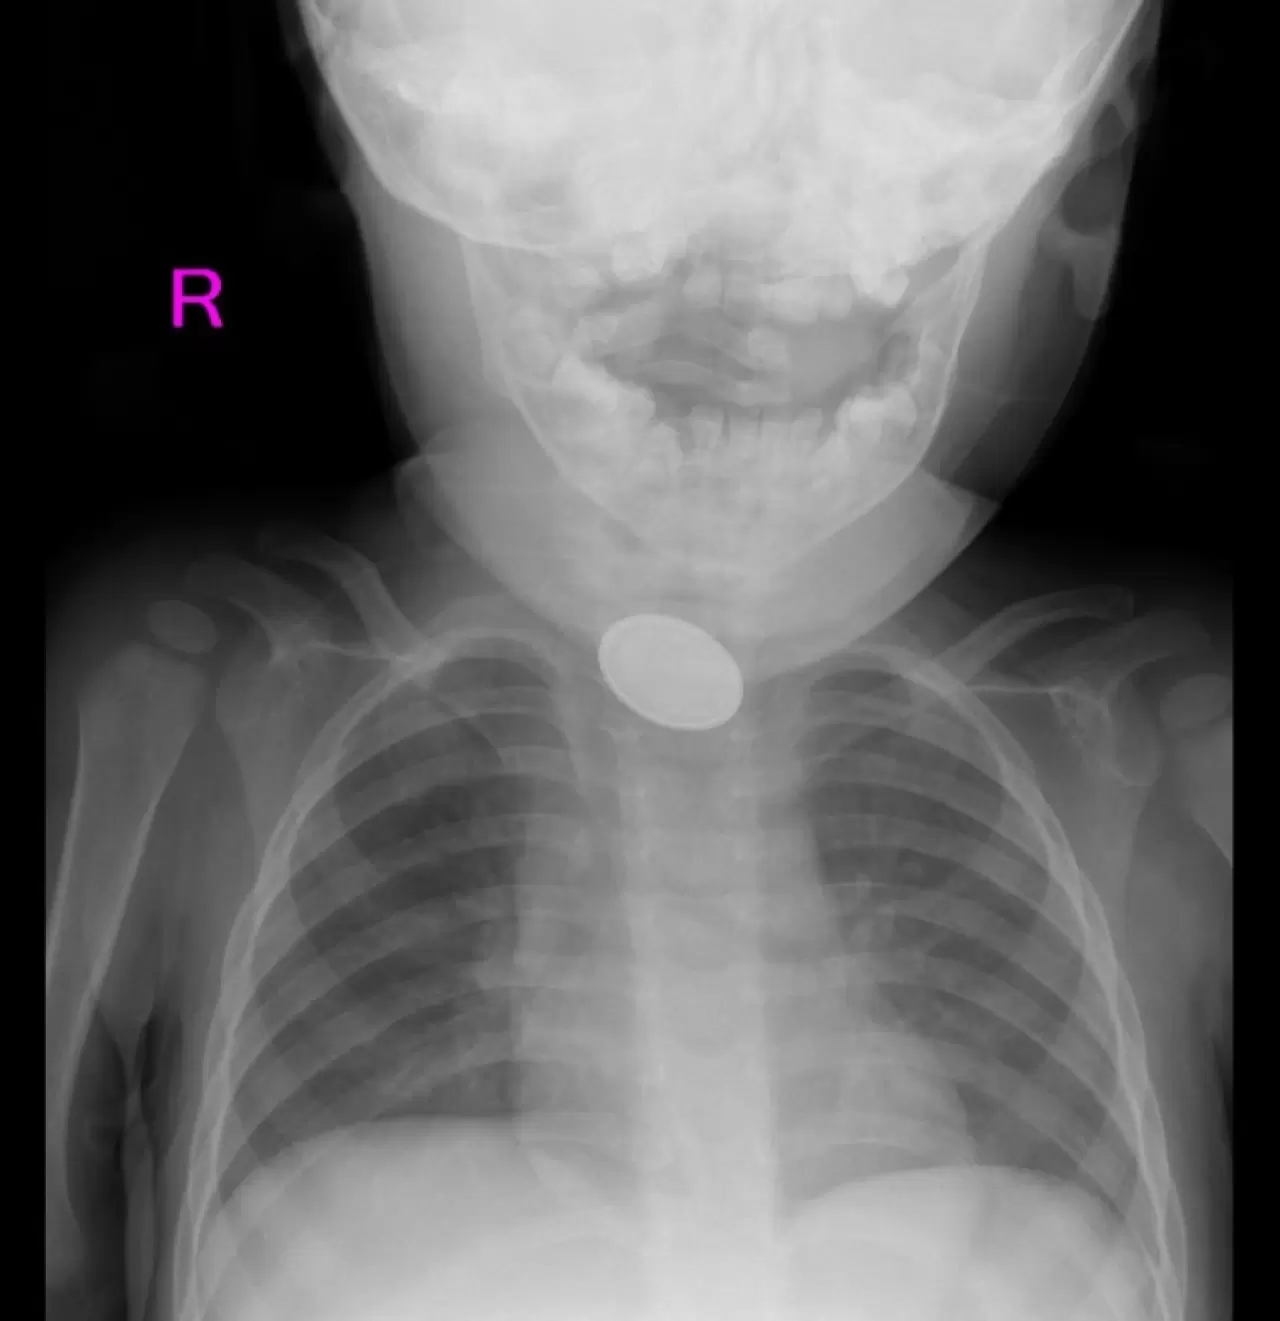

A.Y.Ç.'ye yapılan röntgende, yemek borusunda düğme pil ve lego parçası oyuncağa rastlandı. Kız bebek A.Y.Ç., Kayseri Şehir Hastanesi Çocuk Cerrahisi ve Ürolojisi Anabilim Dalı Başkanı Doç. Dr. Mustafa Erman Dörterler ve ekibi tarafından ameliyata alındı.

Yaklaşık 3 saatlik süren operasyonun ardından A.Y.Ç.'nin yemek borusuna kaçan düğme pil ile lego oyuncak parçası çıkarıldı.